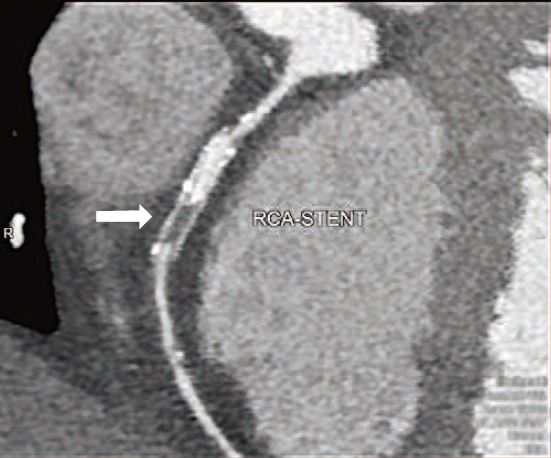

目前CCTA以評估冠狀動脈狹窄為主,但在心臟解剖的正常與否、心肌厚度及引起狹窄的斑塊性質分析也有很大的貢獻。對於曾接受冠狀動脈支架置放術,或是繞道手術的患者,也可有相當不錯的追蹤效果(圖3及圖4)。正在發展中的心肌血流灌注及血流儲備分數(FFR)也愈來愈成熟,指日可待。

圖3:63歲男性,13年前接受右冠狀動脈支架(stent)置放後即戒菸。2020年12月因運動性氣促,接受640切CCTA,發現支架內下半節完全無對比劑顯影(箭號),診斷為支架完全阻塞。